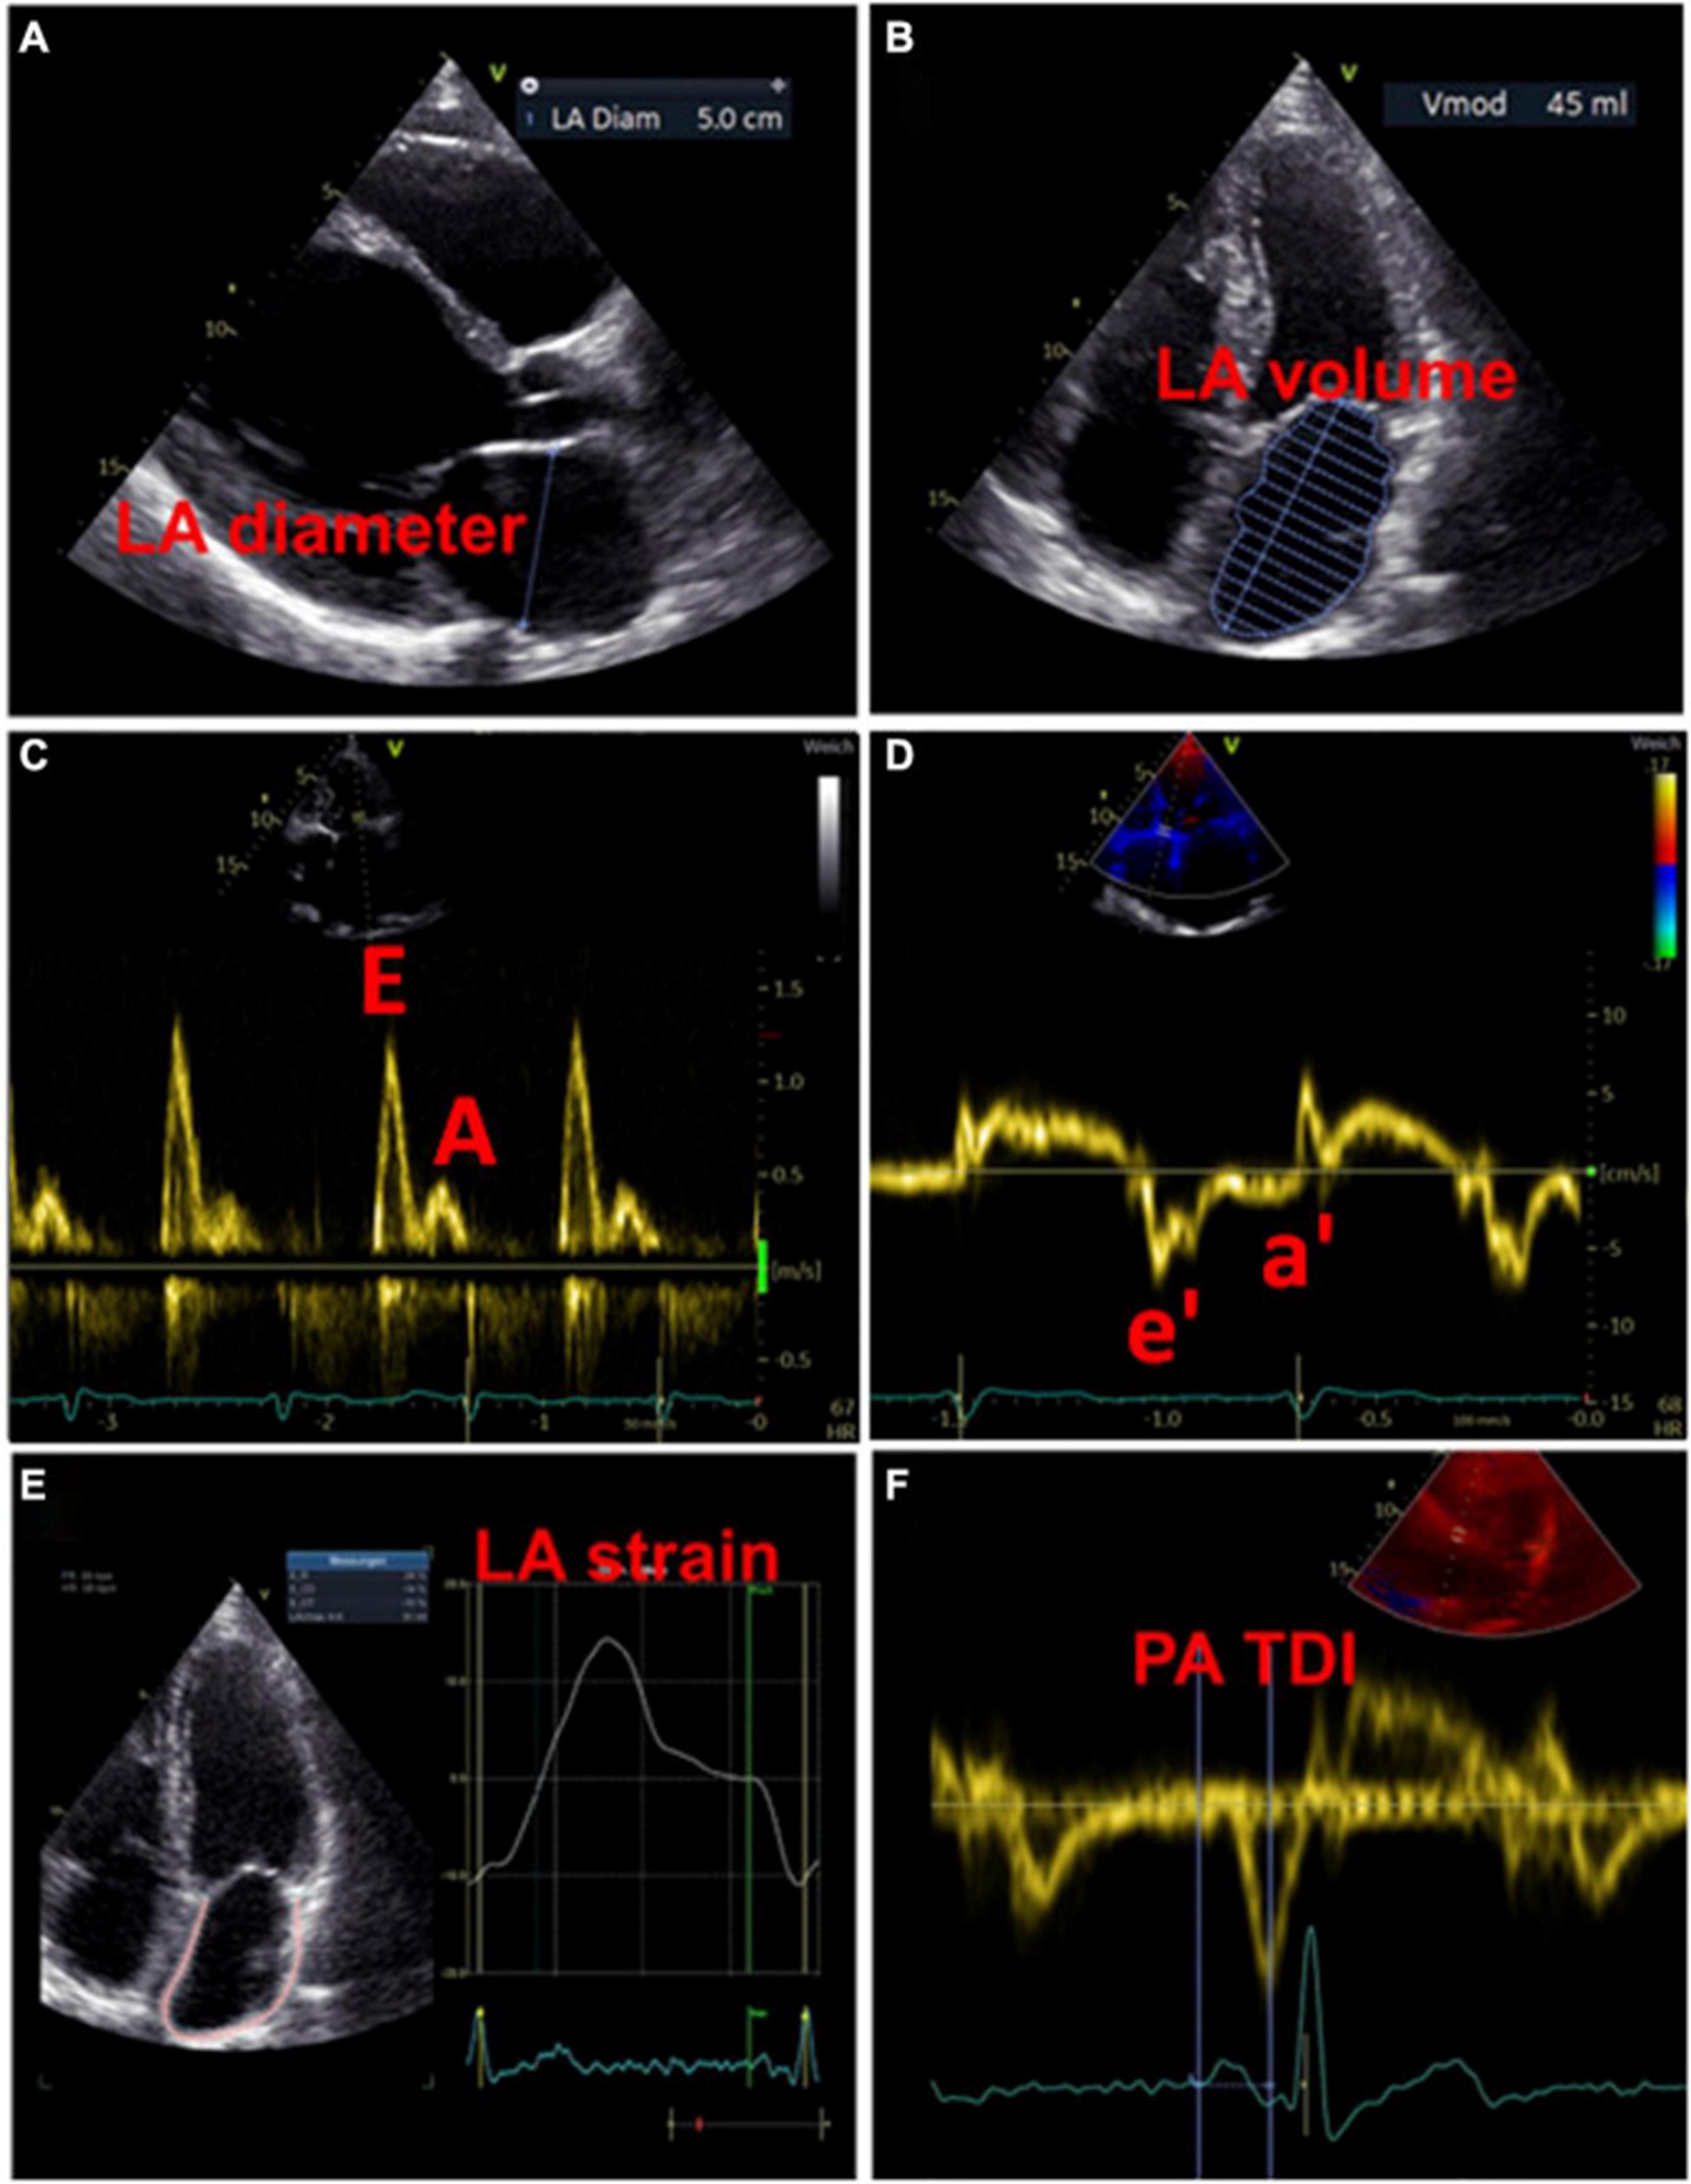

图 3:用于检测左心房心肌病的超声心动图测量示例。(A)测量左心房舒张期的直径。(B)左心房舒张期左心房容积的测量。(C)左心室舒张期的经口流入曲线:第一波代表 E 波(血液被动流入左心室),第二波代表 A 波(左心房主动收缩)。(D)左心室心肌运动的组织多普勒成像,结合(C)心房功能和左心室舒张末期压力的测量结果。(五)左心房的应变分析。(F)测量从 P 波开始(作为心房电活动开始)到 a' 波峰值(心房收缩的机械反应)的 PA-TDI 间隔。

用于估计 LA 大小的一个广泛使用的参数是 LA 直径 (图 3A)。在 AFFIRM 研究中,增加的 LA 直径与复发性 AF 相关,但与卒中风险无关 。然而,一项荟萃分析揭示了较大的 LA 直径与中风和血栓栓塞事件的发生率之间存在关联 。此外,大 LA 直径和 LA 体积指数都被证明是主要不良心血管和血栓栓塞事件的预测参数,特别是在没有 AF 的年轻患者中 。LA 容积指数更精确,因此更适合估计心房大小(图 3B)。增加的 LA 体积指数已被描述为心肌功能障碍的潜在早期标志物,并且经常出现在 AF 患者中,在更高的 AF 负担中频率增加 。此外,与似乎没有预测作用的最大 LA 体积相比,最小 LA 体积与新发 AF 和主要不良心血管事件的发生率密切相关 ( 53 – 56 )。

除了代表结构重构的 LA 大小异常外,心房功能评估可能为左心房心肌病的存在提供进一步的重要指标。LA 扩大和 LA 排空分数降低都是 AF 患者的常见现象,LA 大小与排空分数呈负相关 。最近,Eichenlaub 等人。评估了 AF 患者的 LA 排空分数,用于诊断左心房心肌病和预测 PVI 后心律失常复发 。LACM 定义为心内膜接触标测在 0.5 mV 阈值时LA 低电压区域 ≥ 2 cm 2 。LACM 患者的 LA 排空分数低于没有左心房心肌病的患者(27 对 41%,p < 0.0001)(43)。此外,LA 排空分数 < 34% 是 LACM(曲线下面积为 0.846)和 PVI 后心律失常复发的重要预测因素(57)。

此外,可以通过脉冲波多普勒测量和组织多普勒成像来评估 LA 功能。LA 功能受损可能提示 LACM,在使用多普勒超声心动图的研究中,这与 AF 和 AF 负担等临床结果等同。表格1)。

虽然 LA 传导功能(以二尖瓣 E 波速度为代表)随着 AF 负荷的增加而增加,但 LA 收缩功能(以二尖瓣 A 波速度和二尖瓣环组织多普勒 a' 速度为代表)具有相反的效果。

。早期 [E] 和晚期 [A] 舒张期充盈波的比率增加与 AF 风险之间存在关联。此外,描述了峰值 A 波速度和 AF 风险之间的 U 形关系 。

二尖瓣环“e”波速度降低和 E/e 比增加表明左室舒张功能受损。有证据表明后一个参数也适用于评估 LA 功能和压力 (图 3C、D)。

通过组织多普勒成像持续时间评估的总心房传导时间

通过组织多普勒成像持续时间评估的总心房传导时间,代表超声心动图得出的总心房传导时间,是结构和电心房重塑的吉祥标志,在窦性心律期间测量为 P 波开始之间的时间间隔在表面心电图上的导联 II 和超声心动图上左室侧壁的组织多普勒成像 (TDI) 跟踪上的 A' 波峰值 (图 3F)。PA-TDI 持续时间延长与节律控制干预后新发 AF、术后 AF 和 AF 复发相关 。在 AF 患者中,血栓栓塞风险的评估通过增加 PA-TDI 持续时间值得到改善。迄今为止,尚未建立 PA-TDI 持续时间的标准参考值。然而,如果每个超声心动图实验室通过常规获取 PA-TDI 值来确定自己的正常值,则可能会改善对 AF 相关结果的风险评估 。

斑点追踪超声心动图

近年来,斑点追踪超声心动图已成为通过评估组织运动来检测早期心肌变形的流行方法 。LA 应变和应变率成像提供了对心房功能重塑的见解。图 3E)。评估斑点追踪超声心动图效用的研究主要通过临床定义(例如,AF、AF 负担、AF 复发、血栓栓塞事件)或通过与电解剖标测中的异常发现进行比较来定义 LACM。表格1)。

在严重二尖瓣关闭不全的患者中,通过全球峰值心房纵向应变评估的 LA 纵向变形损伤与 LA 纤维化和重塑程度之间存在很强的相关性 。在 AF 患者中描述了降低的全局纵向 LA 应变,并且是血栓栓塞的预测因子 ( 62 – 64 )。有证据表明,较高的 AF 负担 (≥10%) 与整体纵向 LA 应变的降低特别相关,这与通过映射测量的平均 LA 应变相关,并且可能在 AF 消融后得到改善 。在 Eichenlaub 等人的研究中。(57),预测左心房心肌病的 LA 纵向应变率 < 23.5%,定义为心内膜标测在 0.5 mV 阈值时 LA 低压面积 ≥ 2 cm 2,曲线下面积为 0.878,灵敏度为 92.3%,特异性为 82.4 %。在左心房心肌病患者中,储存期的 LA 应变率显着降低(15.2 对 29.4%,p < 0.0001),并且与左心房心肌病量呈线性相关(43)。